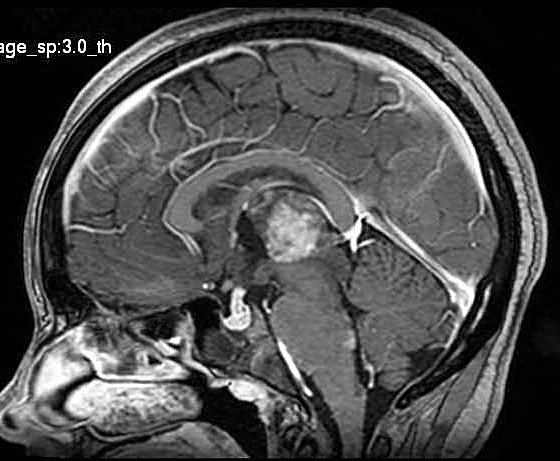

| Fem. 17a. |

| Nódulo sólido homogêneo preenchendo o III ventrículo, com limites precisos, com hipossinal em T1 e hipersinal em T2 e FLAIR, que se impregna por contraste paramagnético. Lesão menor implantada no assoalho do IV ventrículo provavelmente representa disseminação por via liquórica. |

| SAGITAIS, T1 SEM CONTRASTE | T1 COM CONTRASTE | |

| F. 17a. Tumor teratóide rabdóide atípico de III ventrículo. RM | HE | VIM, GFAP | HHF35, desmina, 1A4 | AE1AE3, EMA |